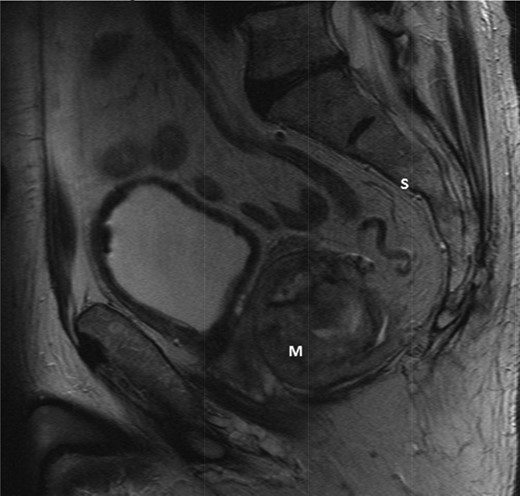

An elderly man in his seventies presented to the Urology department with two episodes of acute urinary retention. There were no rectal symptoms and rectal examination revealed an enlarged prostate. He underwent a laser transurethral resection of prostate during which a large palpable pelvic mass was noted. The subsequent urgent MR pelvis revealed a large tumour in the mesorectum arising from the anterior rectum 10 × 8.5 cm (Figs 1 and 2). A transrectal ultrasound and biopsy were performed; histology revealed a spindle cell tumour, with positive immunostains for CD117 and DOG1 with 5 mitoses per 50 high power fields. This was confirmed to be a locally advanced high-risk GIST.

T2-weighted sagittal image demonstrating a large mass (m) anterior to the sacrum (S) and posterior to the bladder.

T2-weighted axial showing the same mass lying adjacent to the anterior wall of the rectum (*).